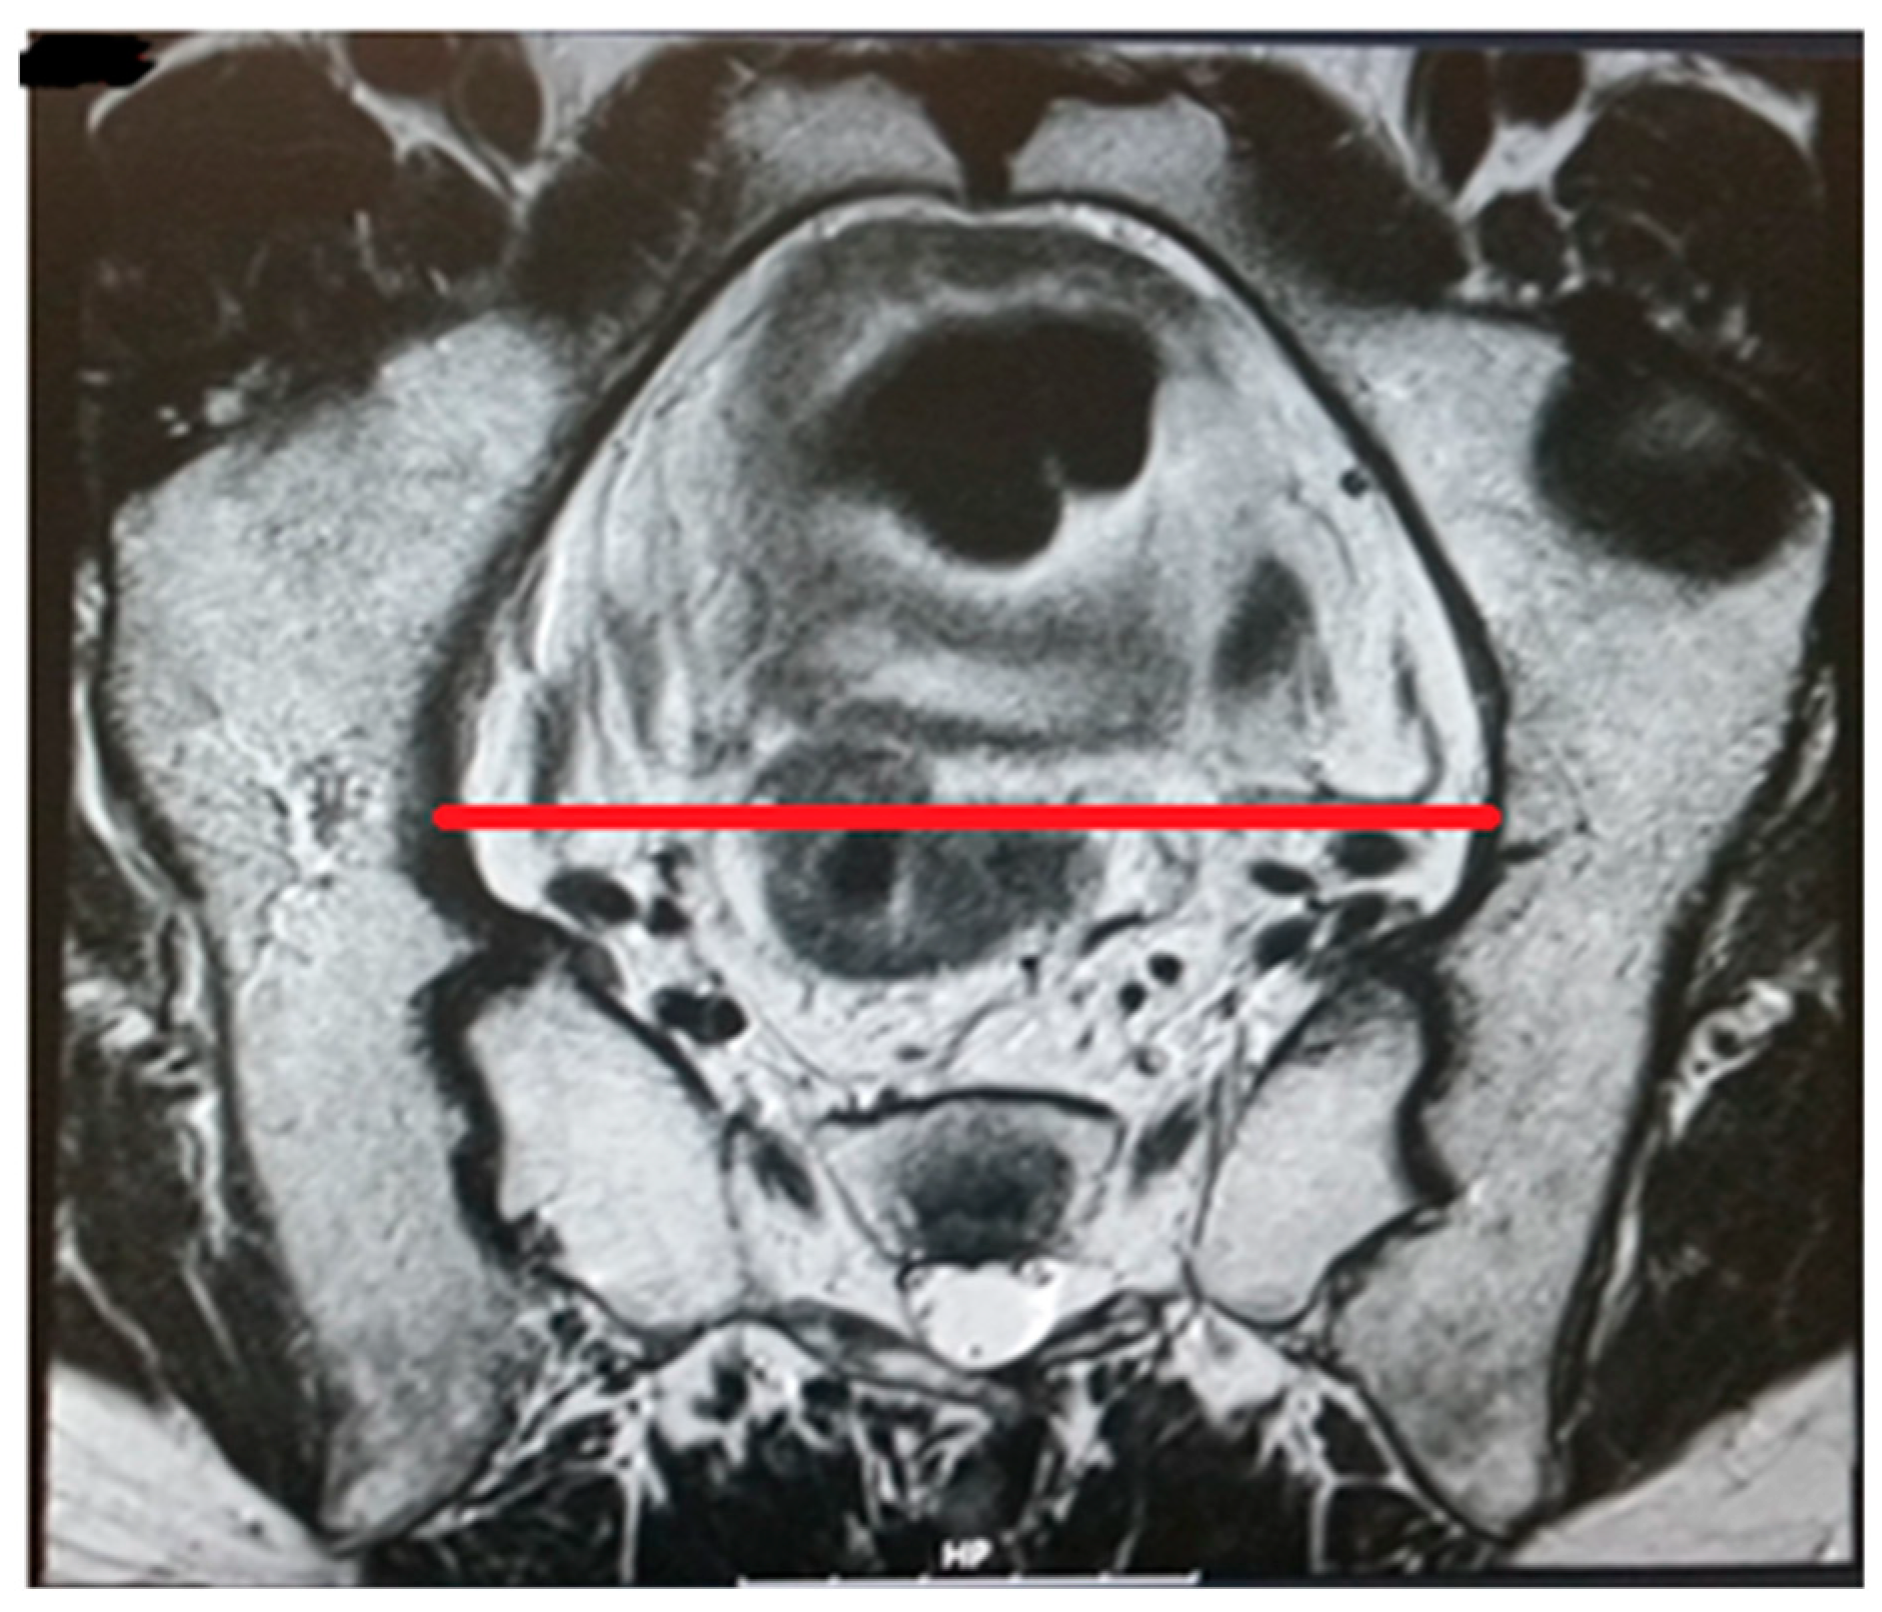

Figure 3.

Transverse diameter.